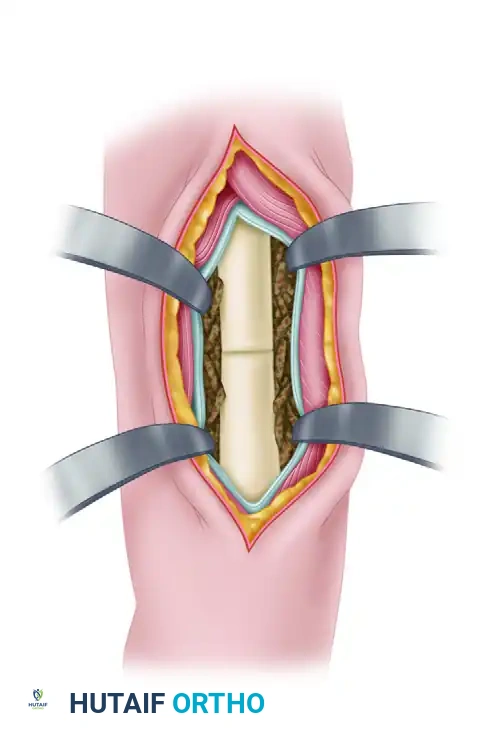

Internal Fixation Using Russell-Taylor Interlocking Nail

- Preparation: Prepare and drape the limb free on a radiolucent operative table to allow unimpeded fluoroscopic access in both anteroposterior (AP) and lateral planes.

- Incision and Entry: If the tibial medullary canal remains in continuity, the fracture site may not require formal opening. Open the entry portal in the proximal tibia (typically via a medial parapatellar or transpatellar tendon approach) using a curved awl.

- Guidewire Placement: Pass a ball-tipped guidewire down to the nonunion site. The proximal tibial shaft can be cautiously reamed to 10 mm to facilitate instrument passage.

- Crossing the Pseudarthrosis: Drive the pseudarthrosis chisel (from the Russell-Taylor interlocking nail set) across the dense fibrous tissue of the nonunion.

- Warning: This step must be performed under continuous AP and lateral radiographic control to prevent the chisel from exiting the tibial canal and causing an iatrogenic cortical breach.

- Distal Canal Access: After successfully opening the nonunion site with the chisel, advance the guidewire into the distal tibial canal from the proximal entry portal.

- Reaming and Insertion: Sequentially ream the tibia to 1.0 mm to 1.5 mm larger than the anticipated nail diameter. Insert the intramedullary nail according to standard technique.

- Locking Strategy: Lock the nail in a dynamic mode. This involves inserting either proximal or distal screws (most commonly distal screws in the smaller fragment), but not both. This allows for axial micromotion and compression at the nonunion site during weight-bearing.

- Implant Selection: Utilize the largest diameter nail that is practically feasible. Nonunions exhibit prolonged healing times, subjecting the implant to extended cyclic loading. A larger nail significantly reduces the risk of fatigue failure compared to standard fresh fracture fixation.